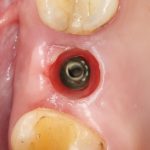

Рекомендации по установке имплантов. Для всех. Часть V.